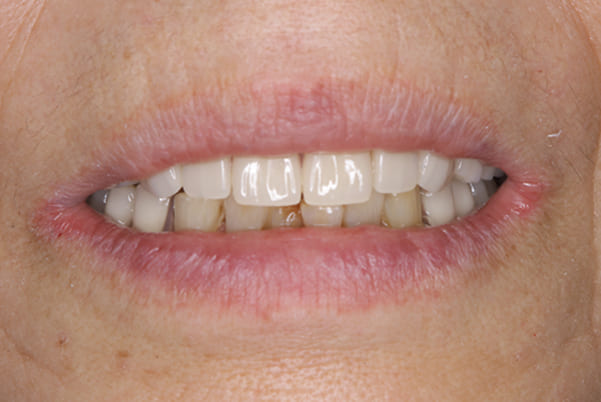

精密義歯

精密義歯は、歯をぬいたあと歯肉が治ってから、精密な入れ歯を作製しました。治療中も、仮の入れ歯があるため、普段の生活に支障がなく、また仮の入れ歯を実際使ってのご意見、ご希望(バネが気になる)をお聞きした上で、精密な義歯に、ご希望を反映し作製しました。

また、当然ではありますが、患者様も残りの歯をこれ以上失いたくないとのご希望が強く可能な限り、残りの歯に負担がかからない機能性を重視し、また、バネがなるべく見えない設計とし、機能と審美の両方に重きをおいた入れ歯を作製し、お痛みなく、お食事も召し上がられるようになりました。